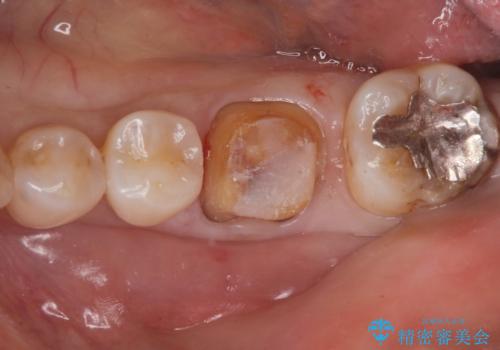

- 奥歯の銀の詰め物が取れたとの事で来院。

詰め物の下に虫歯ができて銀歯が取れてしまった事が予想されます。

白い詰め物でやり直しをしても歯質が薄くなり割れてしまうリスクがあるために、

割れるリスクの少ないジルコニアクラウンにて治療しました。